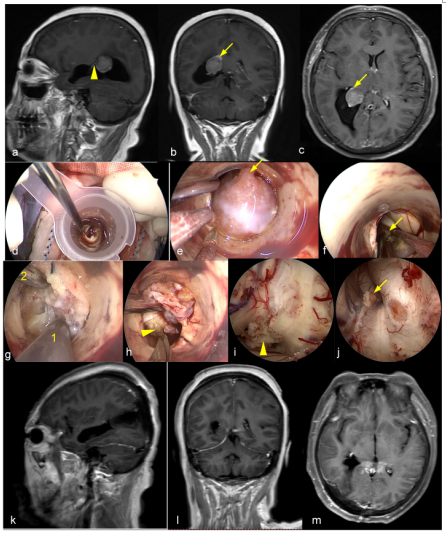

Figure 1. A-C,Pituitary adenoma with bone invasion. A. C preoperative and postoperative MRI. During the surgery, the bone of the jugular tubercle invaded by the tumor was removed. D-L Giant pituitary adenomas. D,F Pre-operation and 1 year post-operation MRI. E Intraoperative bone window exposure range. G.After tumor resection, the normal pituitary gland was preserved.H. After tumor resection, the third ventricle was opened. I The frontal lobe and Anterior communicating artery complex were exposed after tumor resection.K The brainstem and anterior pontine cistern were exposed. J,L. Pre-operation and 1 year post-operation MRI. 1 clivus; 2 Right optic canal; 3 optic canal-internal carotid artery recess; 4. The dura of the planum sphenoidale; 5 Dura of tuberculum sellae; 6. Dura m of sellar floor; 7. Clivus dura; 8. Para-clival internal carotid artery; 9 Third ventricle; 10 Pituitary stalk; 11 frontal gyrus; 12 Anterior communicating artery complex; 13 Brainstem; 14 Basilar artery; 15 Left abducens nerve. The yellow arrow shows the jugular tubercle invaded by the tumor; The untailed yellow arrow shows the normal pituitary gland.